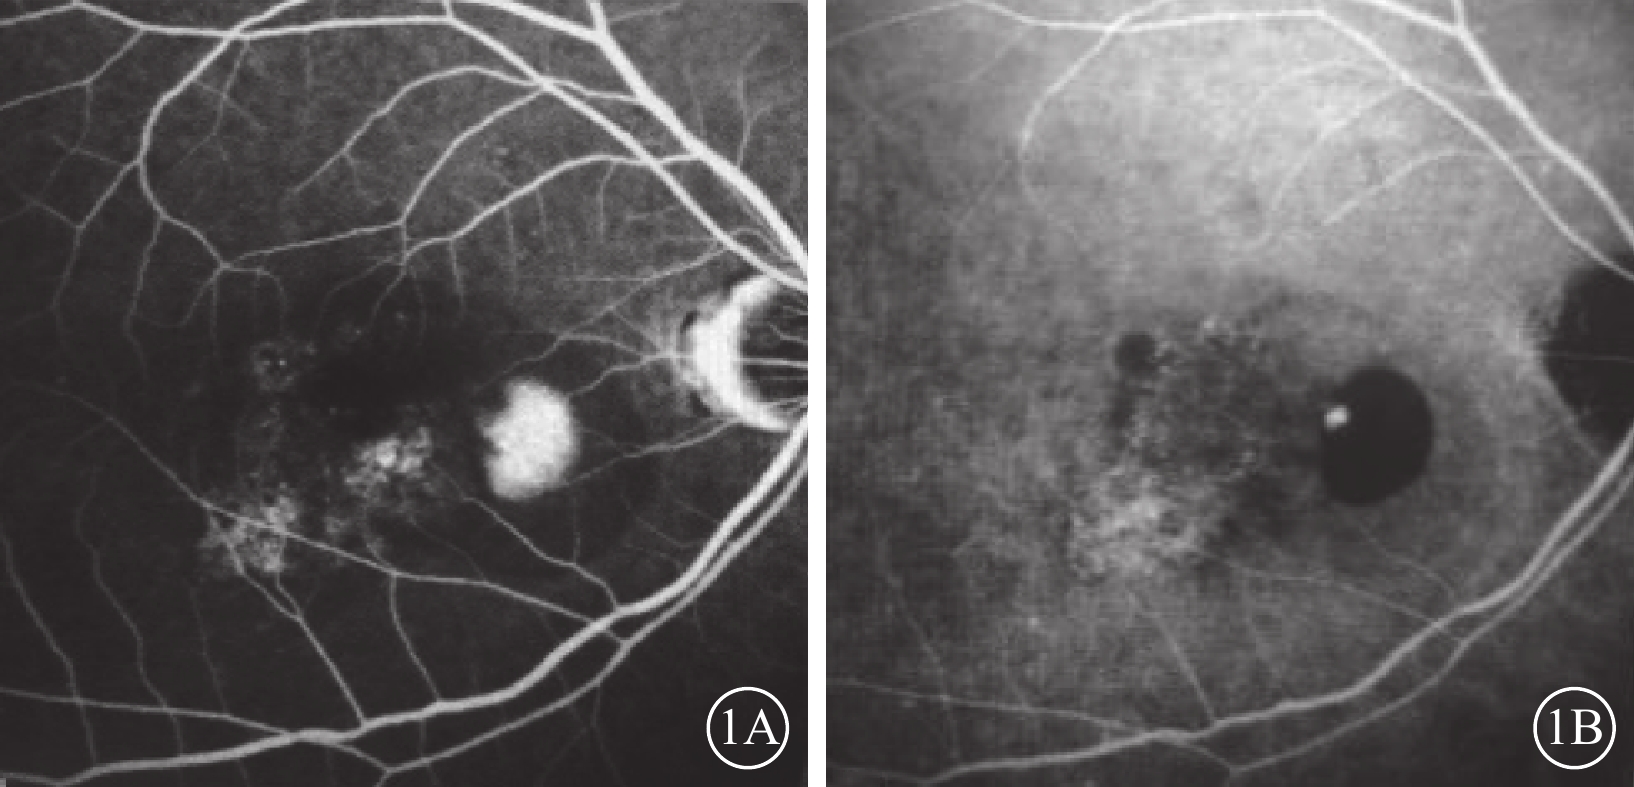

出血性PED在彩色眼底照相中表現為局部片狀或大片狀病灶,顏色從深紅到黑紅不等,周圍可伴滲出(圖3A);在cSLO成像中表現為相應區域的深綠色或暗紅色病灶(圖3B~3E),藍光反射、綠光反射、紅外反射成像均弱,與HD-OCT觀察到的PED位置一致(圖3F)。

出血性PED在彩色眼底照相中表現為局部片狀或大片狀病灶,顏色從深紅到黑紅不等,周圍可伴滲出(圖3A);在cSLO成像中表現為相應區域的深綠色或暗紅色病灶(圖3B~3E),藍光反射、綠光反射、紅外反射成像均弱,與HD-OCT觀察到的PED位置一致(圖3F)。